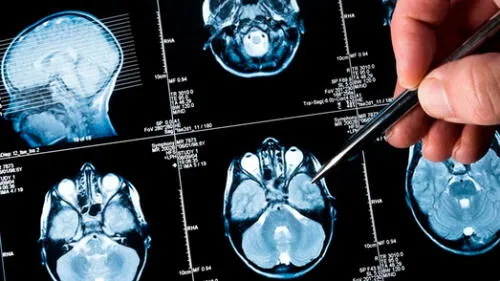

Niña salva de morir luego de que tumor cerebral que tenía desapareció inexplicablemente